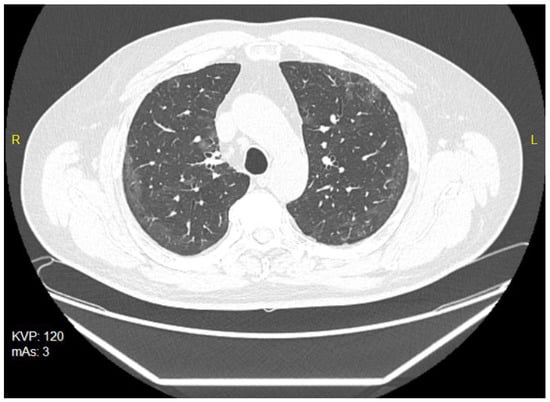

The patient was treated on an outpatient basis, as he complained of cough, breathlessness and fatigue. He was treated with azithromycin administered in a dose of 500 mg for 3 days. The chest X-rays revealed streaky parenchymal densities. The chest CT of 5 February 2021 showed areas of reduced transparency with mainly peripheral distribution, creating locally poorly saturated interstitial ground-glass opacities. There were also visible streaky parabronchial opacities—cicatricial—residual or post-inflammatory, especially at the base of lower lobes of both lungs, and traction of the nearby bronchi, showing slight signs of bronchiectasis (Figure 3). The Aidmed-assisted monitoring was conducted from 10 August 2021 to 23 August 2021. The total duration of the study was 31 h 38 min. The following events were recorded: 93 episodes of Tachypnea (over 25 breaths/min.), 242 episodes of decreased saturation (below 90%) and 716 episodes of tachycardia (over 100 beats/min.) (Table 3). Moreover, on 20 August 2021, during the night monitoring lasting 6 h 28 min, the patient experienced 194 episodes of sleep apnea, mainly in the supine position, and 4 episodes of shallow breathing (Figure 4). The average duration of an apneic episode was 24.02 s, while the longest one went on for 101 s. The AHI (number of apneic and dyspneic episodes) reached 29.98, which corresponds to moderately severe apnea. The lowest recorded blood oxygenation value was 89%, while the total time of saturation below 90% was 52 min.

Figure 3.

The chest CT scan of 5 February 2021—bilateral ground-glass opacities.